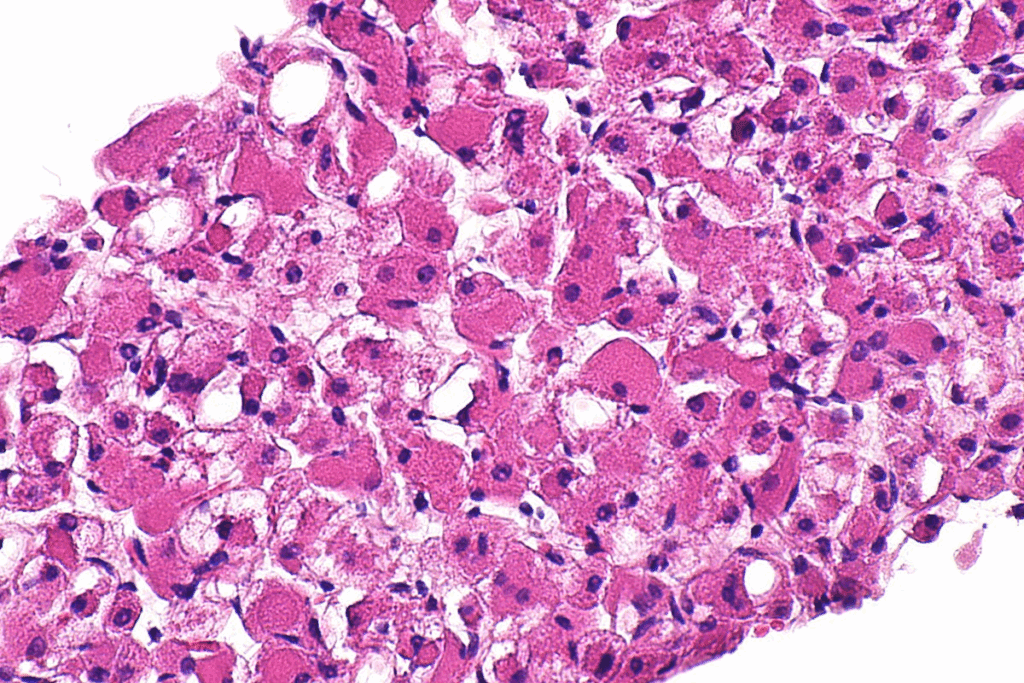

Biopsy and Pathological Examination

A biopsy is vital to confirm rhabdomyosarcoma. A tissue sample is taken and checked under a microscope. Pathologists look for specific signs, like cross-striations, to make the diagnosis.